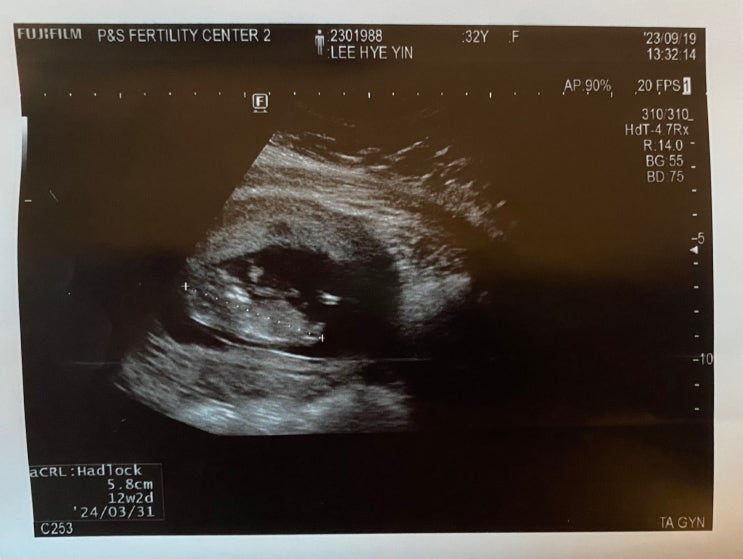

쌍둥이 임신 14-16주차 딸둥이 확정? 2차 기형아검사 감자와눈사람 졸업

10/4(수) 강릉 아이앤맘 피고임 크기 확인 9/25-27 2박3일 입원 후 추석연휴가 지나고 피고임 크기 확인차 ...

감자와눈사람 1차 기형아검사 /피고임 크기 증상 입원

9/7 1차 피고임 출혈(하혈) 이후 피가 멎다- (생리대 말고 팬티라이너 사용할 정도로) 처음으로 피가 팬티 ...